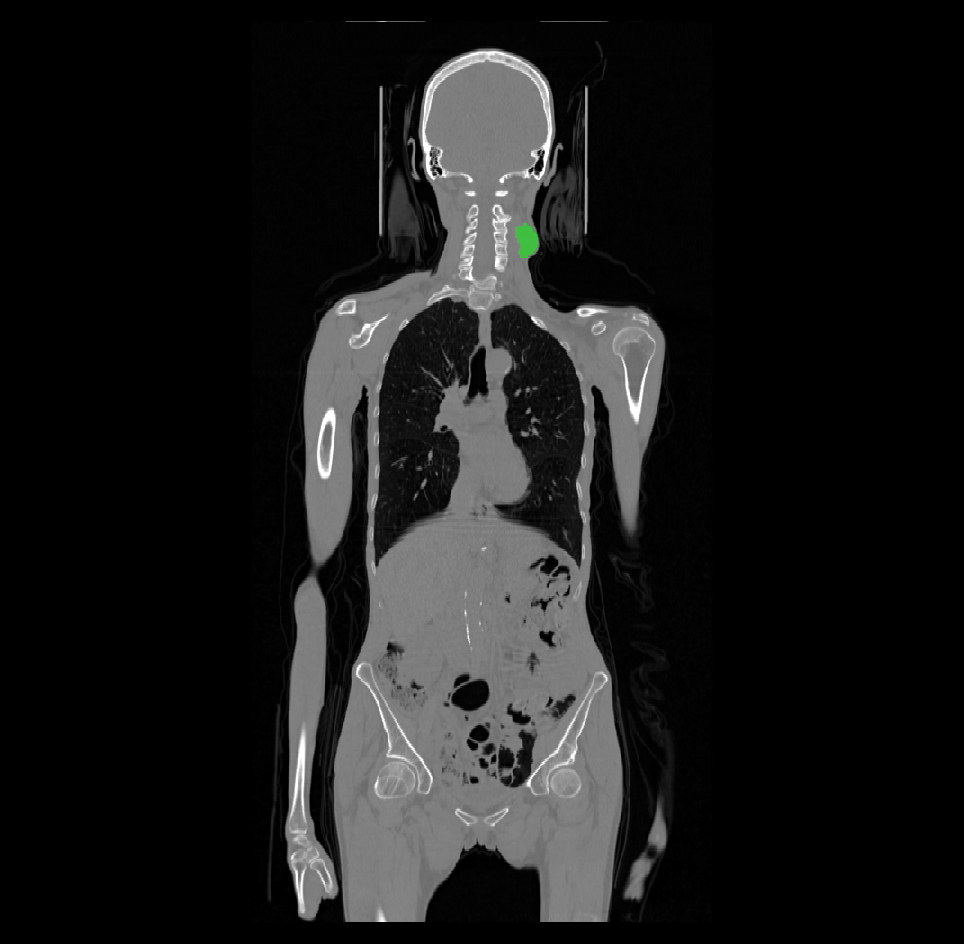

The training dataset with the ground truth labels consists of 524 cases with average 3D CT size of 512x512x200 voxels at 0.98x0.98x3 mm average resolution, and with average 3D PET size of 200x200x200 voxels at 4x4x4 mm. The CT and PET image pairs where rigidly aligned to a common origin, but remain at different sizes and resolutions. Many cases provided were almost a full body CT/PET pairs. This provides both computational and algorithmic challenge, since the imaging region is as large as 500x500x1000 mm of the body anatomy, whereas the tumor region covers less then 5% of the input images.

The ground truth labels usually include a single mass of the primary tumor (but in some cases it was absent completely or had two components), and several connected components of the annotated lymph nodes. An example case of CT and the corresponding PET image with ground-truth overlays is shown in Figures 1 and 2.